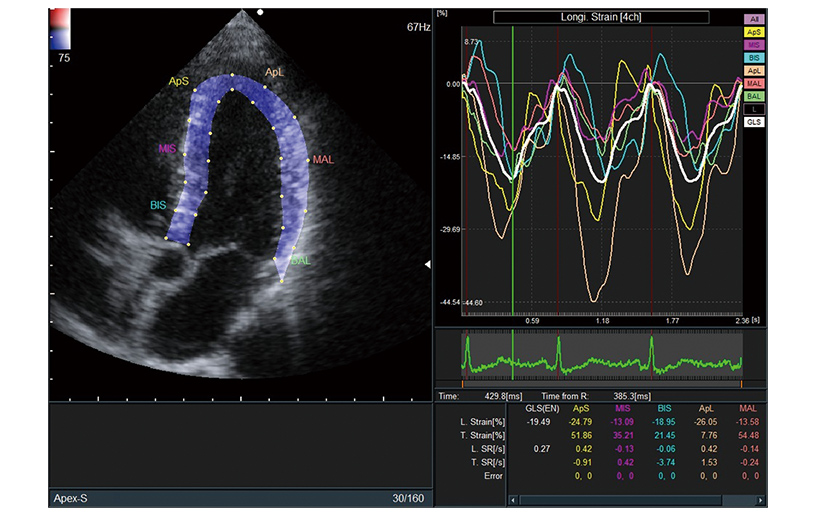

Deformação longitudinal global (Global Longitudinal Strain, LSG)

Tem havido interesse recente no LSG, a razão de variação do comprimento do endocárdio do LV, que pode estar significativamente alterado em doentes com insuficiência cardíaca mesmo quando é mantida uma fração de ejeção (Ejection Fraction, FE) normal.

Rastreio de tecidos 2D (2DTT) *1

Técnica de rastreio de manchas que quantifica e analisa o movimento de todo o ventrículo esquerdo ou movimento local do miocárdio.